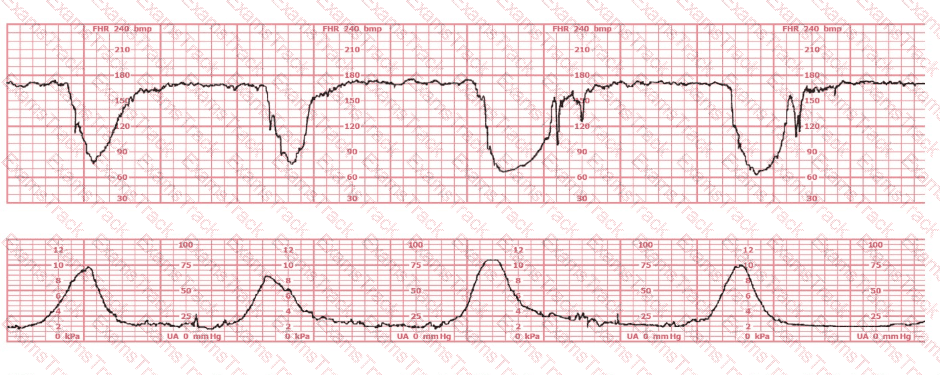

After spontaneous rupture of membranes, this fetal heart rate pattern is observed. The initial intervention should be to:

A woman at 39-weeks gestation is in early labor, 2–3 cm dilated, 85% effaced, and –2 station. Based on the fetal heart rate tracing shown, what is the most appropriate first intervention?